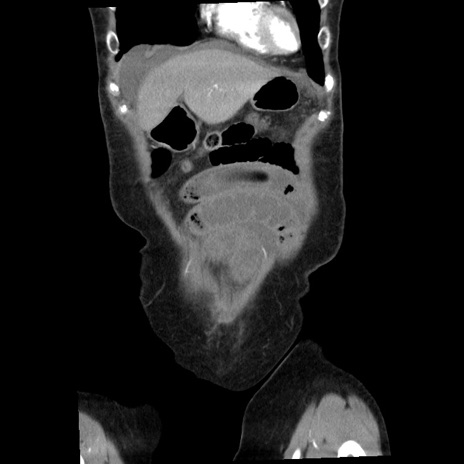

矢状断像

【症例】80歳代女性

【主訴】腹痛

【現病歴】8時間前から腹痛あり来院。

【既往歴】糖尿病、脂質異常症、子宮体癌にて子宮全摘術

【身体所見】意識清明・会話良好だが腹痛で苦悶様、全腹部にわたって反跳痛と圧痛あり

【データ】WBC 13600、CRP 0.14、LDH 224、CK 90